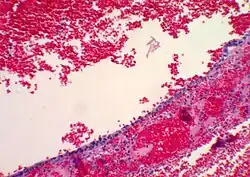

| Functional cyst | Follicular cyst |

| |